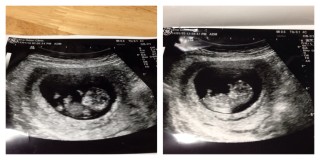

3週間ぶりの検診。 不安で同じ週数の方のエコー写真を見て なるべく前向きに過ごしました。 いざエコーで見ると、私の心配をよそに元気に動く赤ちゃん。 CRL36.1mm、少し大きめの元気な赤ちゃんと説明してもらえて 嬉しかったしホッとしました。

でもエコーで大きくなったところを確認できるとテンション上がります。32.4mmで大きく育ってくれて一安心^ ^